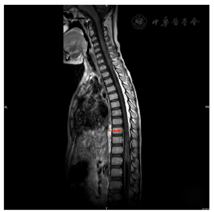

2021年7月16日胸椎MRI:胸7~9椎体水平以下脊髓信号异常,增强后示病灶强化不明显。2021年7月27日胸椎MRI增强(图1)提示胸9~10脊髓及脊髓圆锥内异常信号,出血?2021年8月10日MRI增强(图2)诊断为急性脊髓炎。2021年8月26日MRI增强(图3)提示急性脊髓炎伴脊神经炎,较前有所好转。2021年12月20日胸椎MRI增强(图4)提示急性脊髓炎伴脊神经炎,较2021年8月26日范围稍缩小。